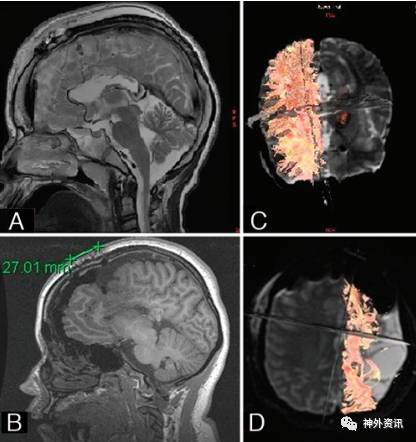

6例患者胼胝体切开术的时间2-3h,大脑半球离断术的时间4-5h。术中出血不多,均未输血,平均住院时间4天。术后颅脑MRI和MRI-DTI成像确认胼胝体完全切开和大脑半球离断(图4)。术后平均随访6±2.1个月,跌倒性发作症状消失;大脑半球离断术患者无癫痫再发作。

图4. 术后MRI和MRI-DTI。A.胼胝体切开术后MRI矢状位T2图像;B.大脑半球离断术后MRI矢状位T1图像;C.胼胝体切开术后MRI-DTI成像;D.大脑半球离断术后MRI-DTI成像。